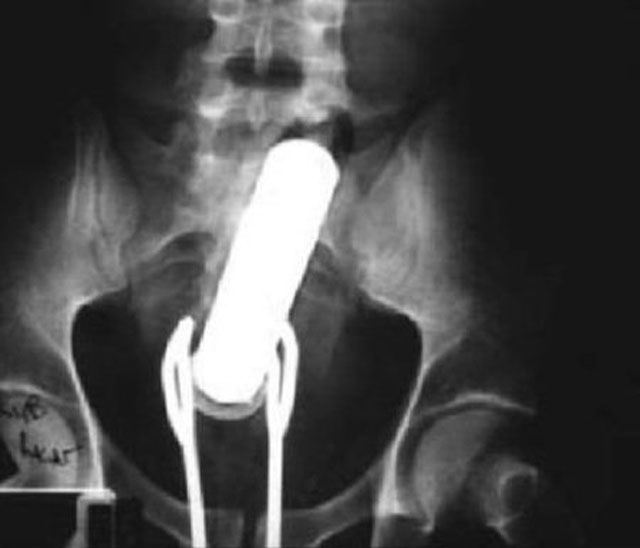

Getting a vibrator stuck in his bum wasn't enough to send this man to the ER. He simply attempted to remove the stuck object by using a pair of salad tongs. Trouble is, then the tongs got stuck, too!

This incident was not an accident, it was intentional. The late Ryan Dunn of the television show Jackass intentionally inserted a Matchbox car into his rectum just to mess with the ER doctors.